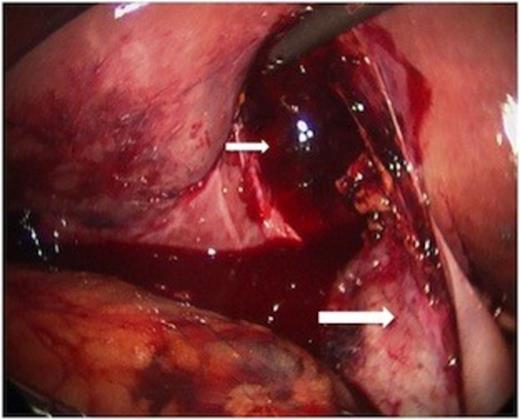

While hepatic contrast extravasation in a stable patient is typically treated with angioembolization, proximity to the gallbladder was concerning for gallbladder injury. Exploratory laparoscopy was performed and the gallbladder was found to be perforated and nearly completely avulsed from the liver (Figures 2 and 3).

At laparoscopy, the gallbladder (large white arrow) was found partially avulsed from the gallbladder fossa (small white arrow).